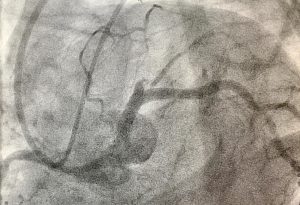

Na quarta-feira (17/04), o serviço de Hemodinâmica do HCFAMEMA (Hospital das Clínicas da Faculdade de Medicina de Marília) realizou o primeiro procedimento de angioplastia coronariana por via retrógrada, da região.

O procedimento realizado pela equipe do Prof. Dr. Igor Ribeiro de Castro Bienert e Prof. Pedro Beraldo, consiste em contornar todo o coração através das coronárias, vasos que nutrem o coração, de um lado ao outro, para desobstrução de lesões que provocam infarto do miocárdio e que não puderam ser tratadas por técnicas convencionais de cirurgia.

A técnica foi desenvolvida no Japão e é uma alternativa eficaz para pacientes com obstrução total crônica grave.